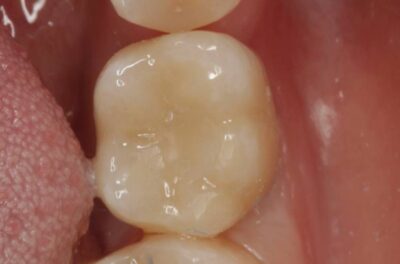

Специализация: терапия(эндодонтия), ортопедия, имплантология.